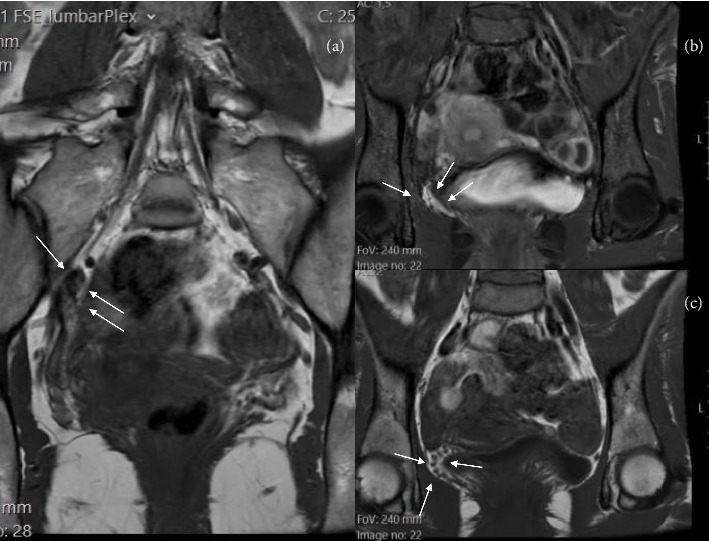

Pelvic congestion syndrome (PCS) is an underdiagnosed but not rare cause of chronic pelvic pain, affecting approximately 10%-30% of women of reproductive age. It is characterized by venous insufficiency and dilation of the ovarian and pelvic veins, often presenting with symptoms that worsen during menstruation or prolonged standing, and improve in the supine position. Dyspareunia and a sensation of pelvic heaviness are also frequently reported. Neurological manifestations-such as pudendal or femoral nerve irritation-are rare but may offer key diagnostic clues. We present a case of a 30-year-old woman with right-sided pelvic pain radiating to the groin and proximal thigh, consistent with neural irritation. Magnetic neurography revealed dilated pelvic veins in close proximity to the right psoas muscle and the L5 nerve root, suggesting perineural venous engorgement. Selective venography confirmed bilateral ovarian vein insufficiency, and the patient underwent successful embolization with Ruby coils and adjunct sclerotherapy. Postoperative recovery was uneventful, with complete resolution of symptoms. Follow-up at 1 year showed no recurrence, and the patient later achieved a successful pregnancy. This case highlights the potential for pelvic venous congestion to mimic or cause neural symptoms and emphasizes the diagnostic value of magnetic neurography in complex pain presentations. Endovascular treatment proved safe and effective, even in cases with neurological involvement.